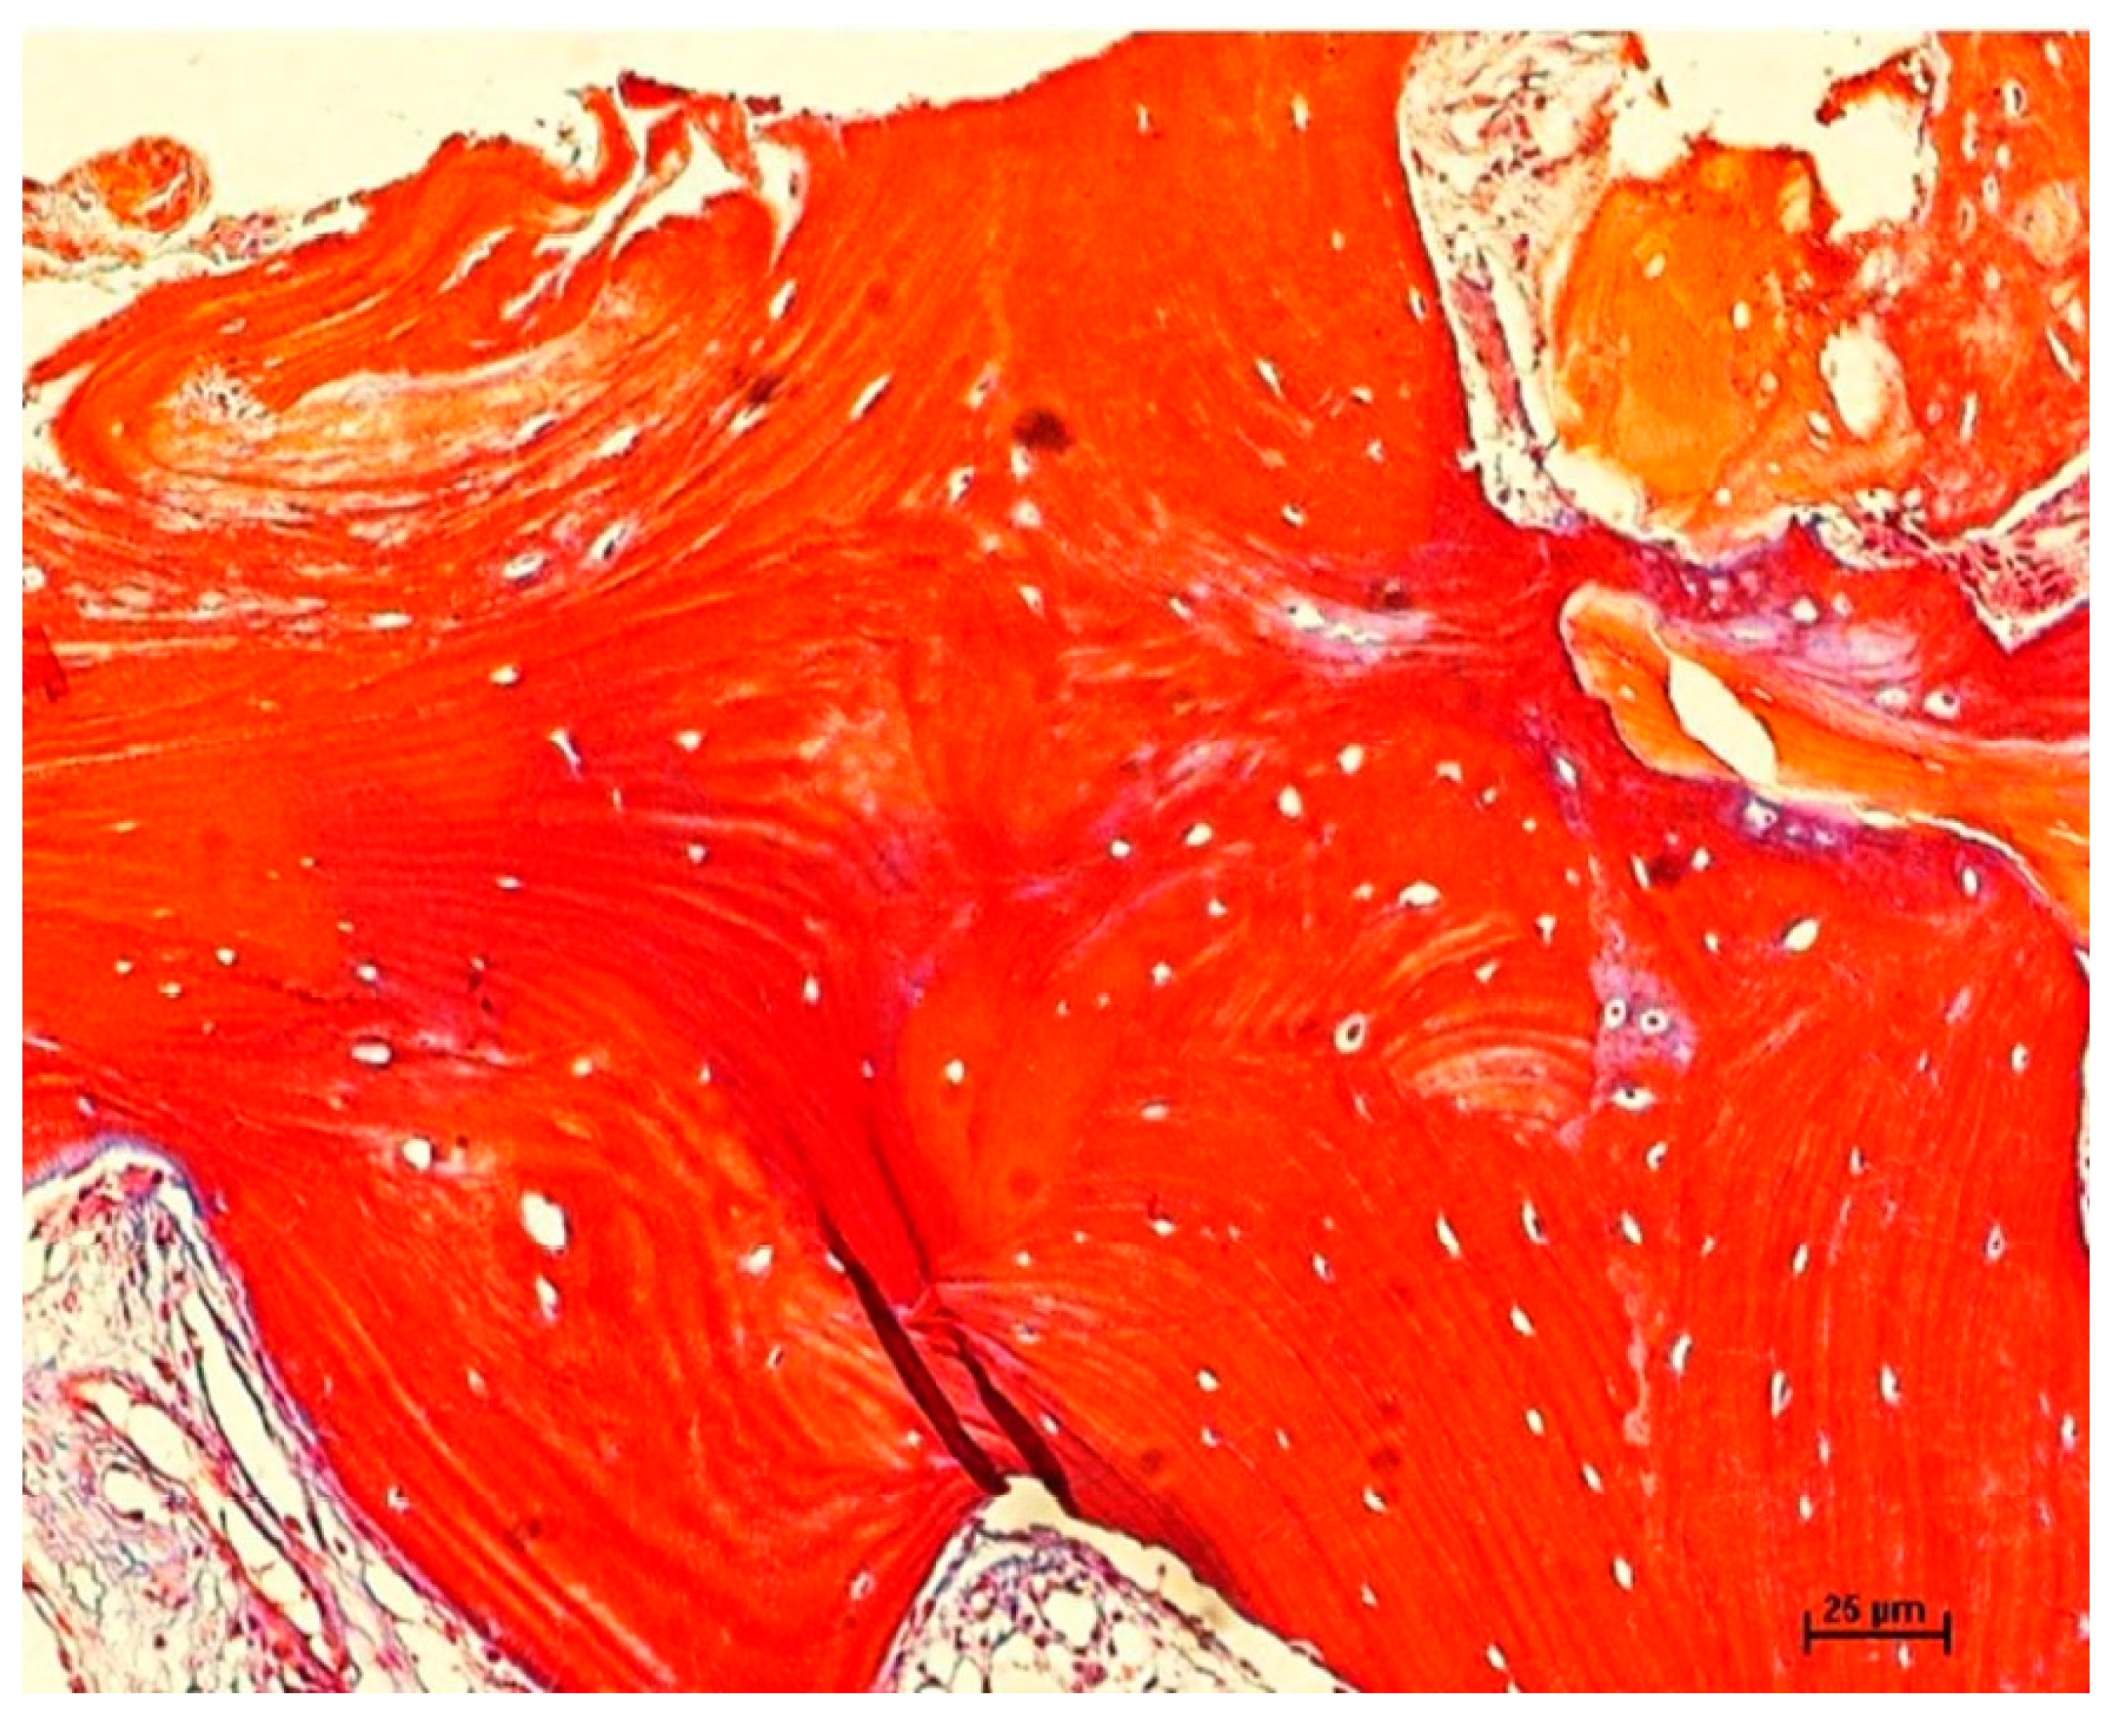

2.5. Bone Biopsies

2.6. Histomorphometric Evaluation